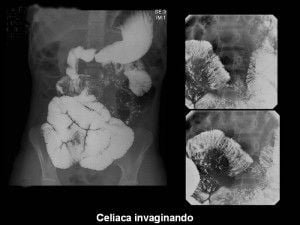

Abdomen, aparato digestivo y via biliarTécnicas de Exploración Radiológica Tránsito del intestino delgado Parte II 28 junio, 2012 Tidito Transito intestinal contraste simple Transito intestinal doble contraste yeyuno e ileon Patologia de Transito intestinal – Enfermedad celiaca Tumor maligno ileon terminalEnfermedad inflamatoria intestinal